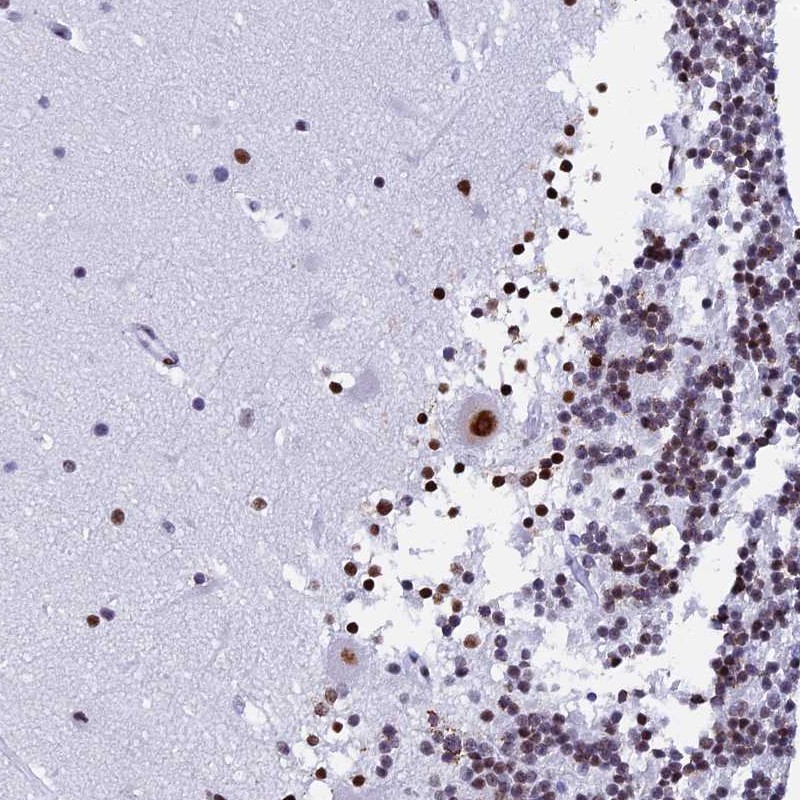

Immunohistochemical staining of human cerebellum shows strong nuclear positivity in Purkinje cells.